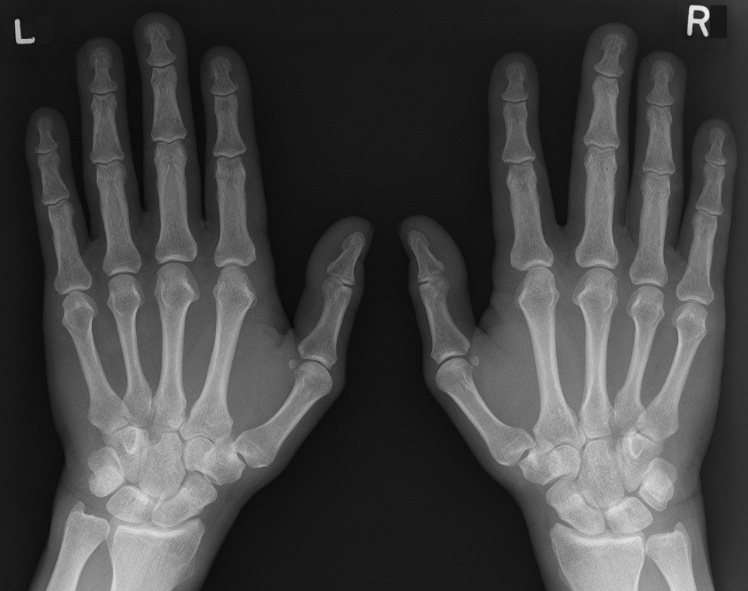

Raynaud’s disease الفيزياوي كرار حيدر عبد الحسين

<br />يُصيب داء رينو بعض المناطق في جسمك - كأصابع اليدين والقدمين - بالخَدر والبرودة في حالة انخفاض درجات الحرارة أو التوتر. يؤدى داء رينو إلى تضُّيق الشرايين الصغيرة التي تمد الجلد بالدم؛ ما يحد من تدفق الدم إلى المناطق المصابة <br />تكثر الإصابة بداء رينو بين النساء عن الرجال، ويُعرف أيضًا باسم ظاهرة رينو أو متلازمة رينو. ويبدو أن هذا المرض أكثر شيوعًا بين من يعيشون في المناطق الباردة.<br />يعتمد علاج داء رينو على مدى حدة المرض وما إذا كنت مُصابًا بأي حالات صحية أخرى. بالنسبة لمعظم الناس، فإن مرض رينو لا يُعيق حياتهم، لكنه يمكن أن يُؤثِّر على جودة الحياة.<br />تتضمن مؤشرات وأعراض مرض رينو ما يلي<br />برودة أصابع اليدين أو القدمين*<br />تغيُّرات في لون الجلد استجابة للبرودة أو الإجهاد*<br />خدر أو شعور شائك أو وخز عند الاحترار أو تخفيف التوتر*<br />أثناء نوبات مرض رينو، عادةً ما تتحول المناطق المصابة من جلدك إلى اللون الأبيض أولاً. ثم يتحول لونها غالبًا إلى اللون الأزرق وتشعر بالبرد والخدر. وعندما تدفأ وتتحسن الدورة الدموية، قد يتحول لون المناطق المصابة إلى الأحمر أو تشعر بنبض بها أو تصاب بالخَدَر أو التورم.<br />على الرغم من أن مرض رينو يؤثر في أغلب الأحيان على أصابع اليدين والقدمين، فقد يؤثر أيضًا على مناطق أخرى من الجسم، مثل الأنف والشفاه والأذنين . وبعد التدفئة، يمكن أن تستغرق عودة تدفق الدم الطبيعي إلى اجزء الجسم 15 دقيقة.<br />الوقاية<br />للمساعدة في تجنب الإصابة بنوبات رينو<br />ارتدِ ملابس للتدفئة في المناطق المكشوفة. عندما يكون الطقس باردًا، ضع قبعة ووشاحًا وارتدِ الجوارب والحذاء ذي الرقبة الطويلة والقفازين قبل الخروج. ارتد المعطف المزود بأساور أكمام مريحة بحيث يلتف على غطاء يديك لمنع تسرب الهواء البارد إلي يديك.<br />استخدم مدفئات الأيدي الكيميائية. ارتدِ واقيات الأذن وقناع الوجه إذا كانت شحمة أذنك أو طرف أنفك حساسًا للبرد<br />شغل جهاز التدفئة في سيارتك. شغل مدفئة سيارتك لعدة دقائق قبل القيادة في الطقس البارد.<br />اتخاذ الاحتياطات بالأماكن الداخلية. ارتدِ الجوارب. ارتدِ قفازين عاديين أو قفازين سميكين عند إحضار الطعام من الثلاجة أو المُجمِّد (الفريزر). يفضل البعض ارتداء القفازات والجوارب قبل الخلود إلى النوم في فصل الشتاء.<br />اضبط مكيف الهواء على درجة حرارة دافئة لأن مكيف الهواء يمكن أن يزيد من حدة تلك النوبات. استخدم الأكواب ذات الطبقة العازلة<br />